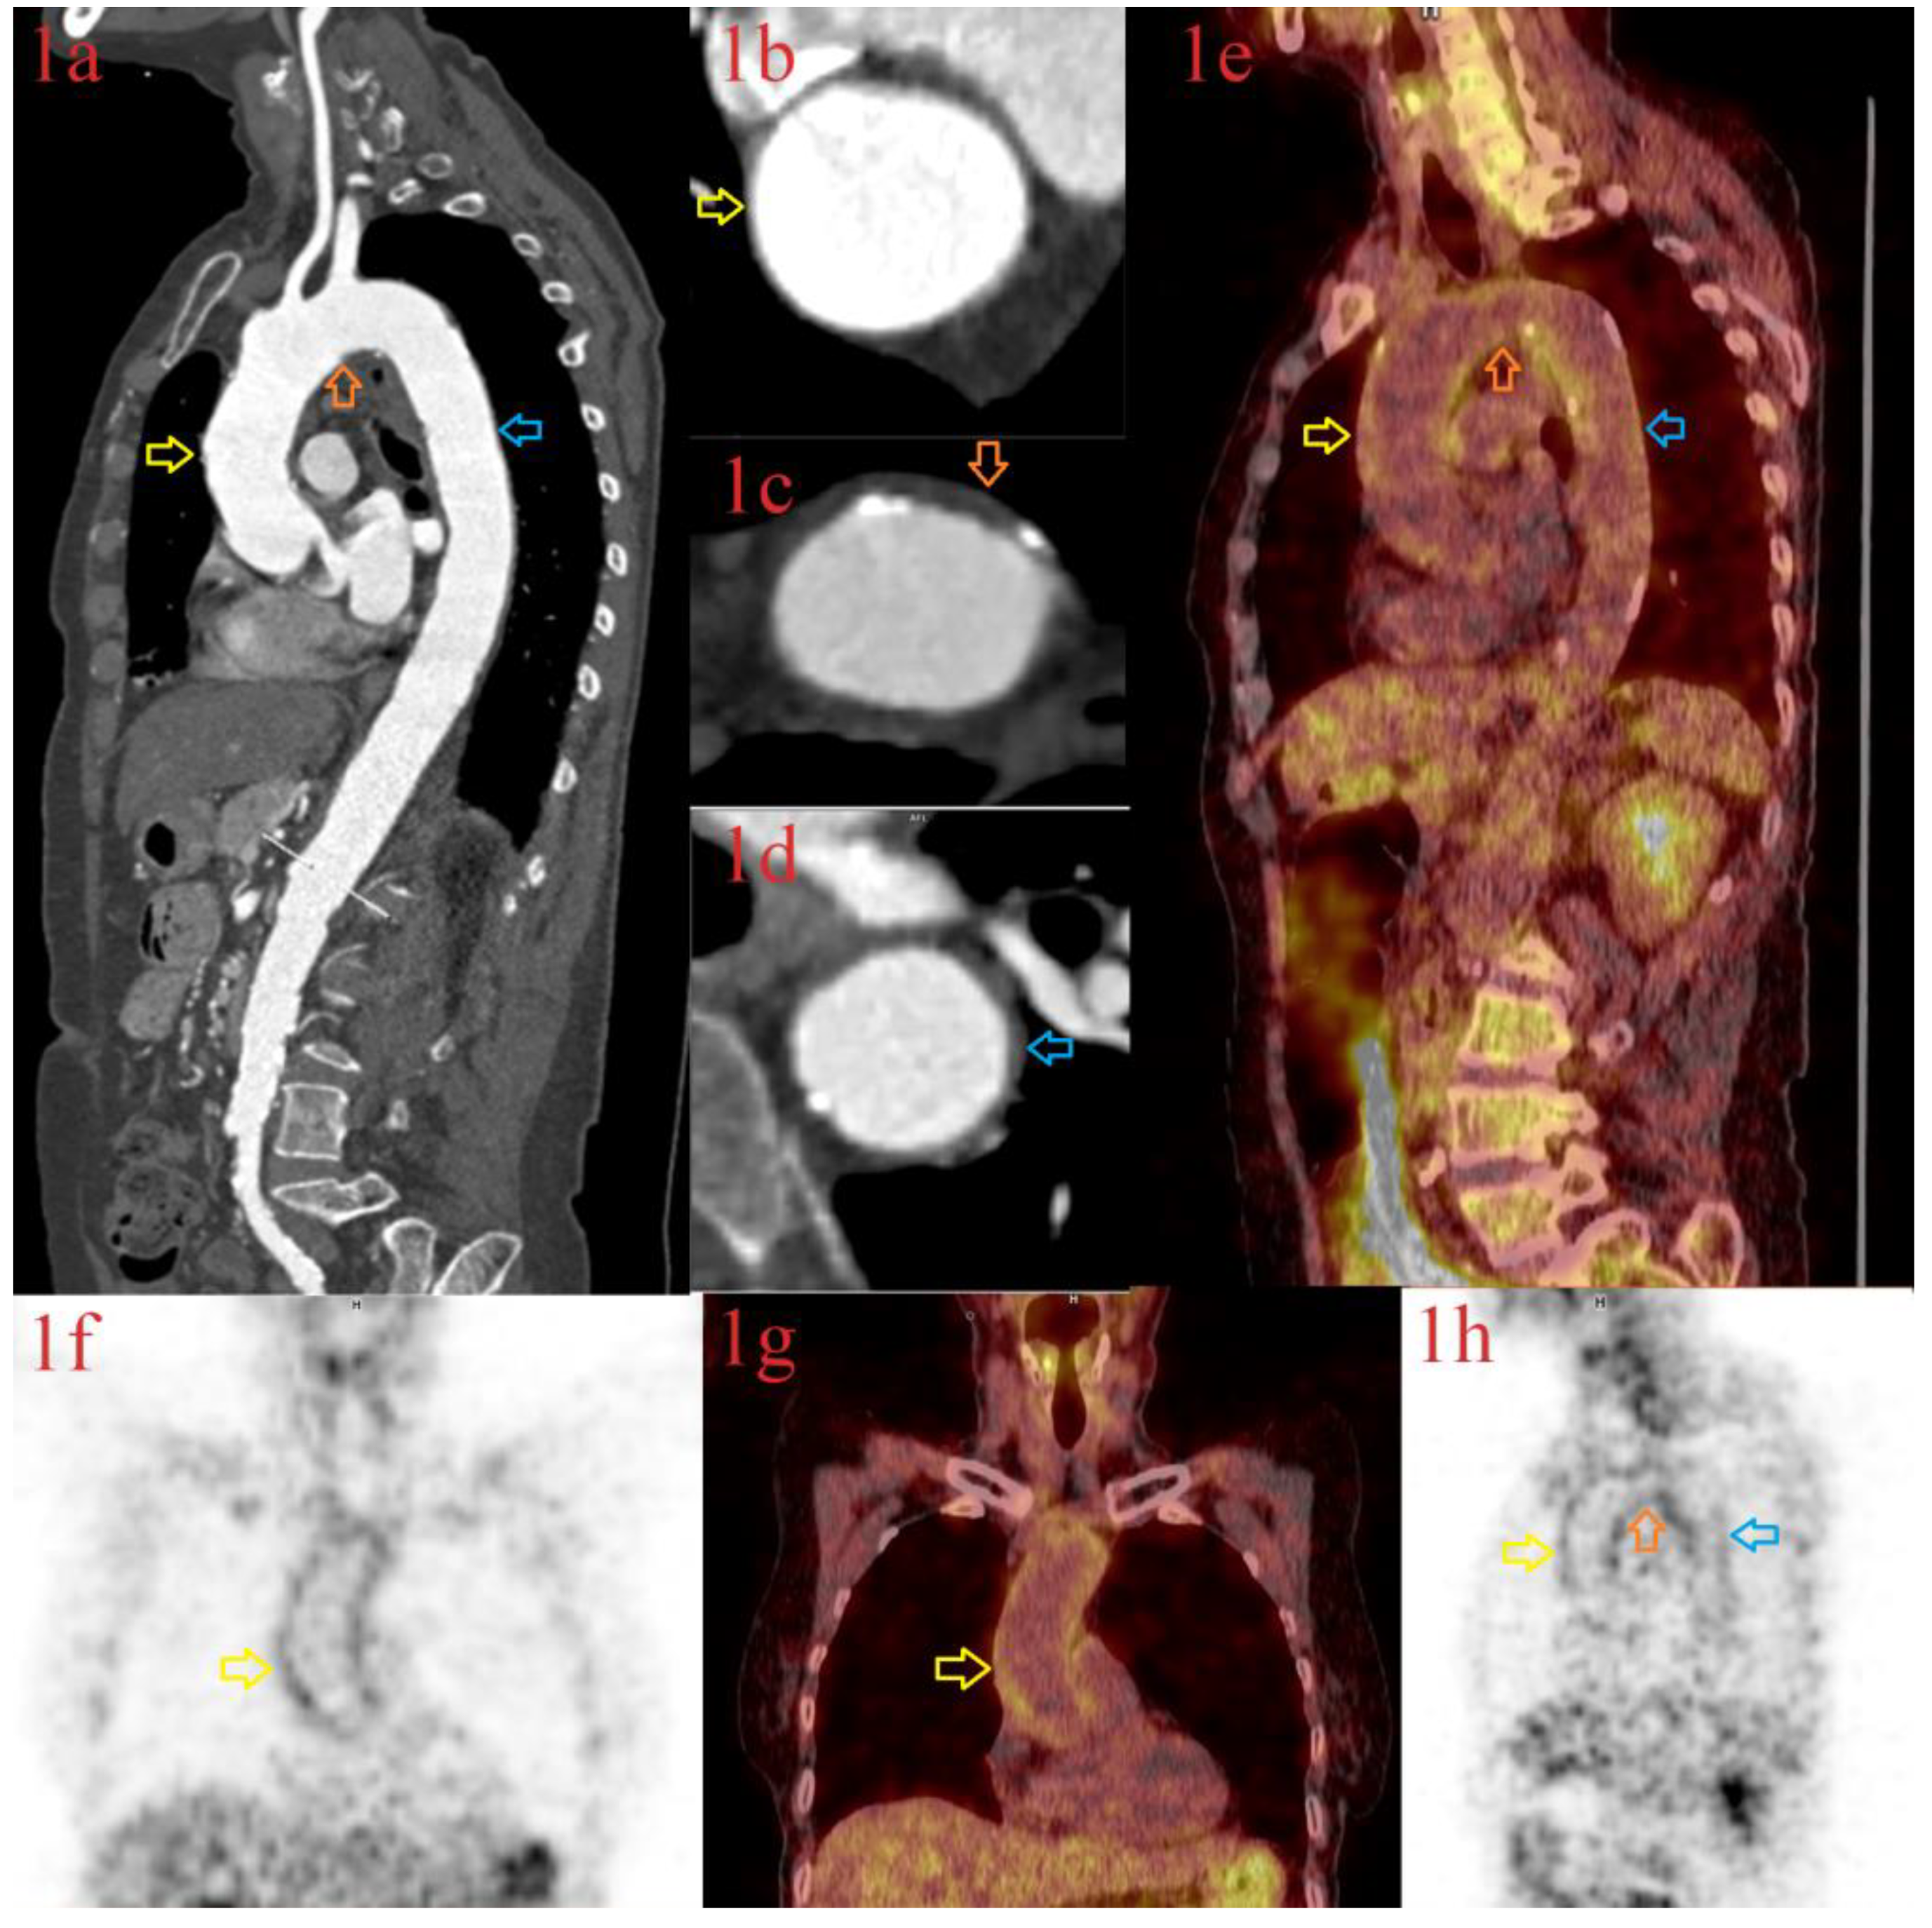

3.1.1. Patient 1

3.1.2. Patient 2

3.1.3. Patient 3